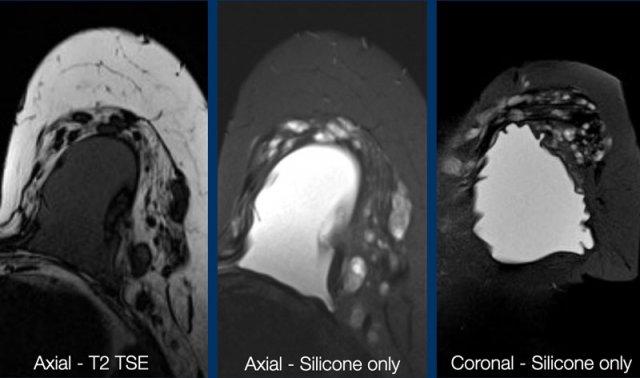

Một ví dụ khác về vỡ túi ngoài bao xơ với silicone nằm ngoài ranh giới bao xơ.

Bệnh nhân này đã được phẫu thuật tháo túi độn ngực hai bên.

Bên phải có tín hiệu cao của vật liệu silicone trong các hạch bạch huyết (mũi tên trắng).

Bên trái có silicone tồn dư ở phía trước và phía sau cơ ngực lớn (mũi tên vàng) và cả bên trong cơ.

Khi một túi độn silicone mới được đặt vào, lượng silicone tồn dư này không nên bị nhầm lẫn với tình trạng rò rỉ ngoài bao xơ của túi độn mới.